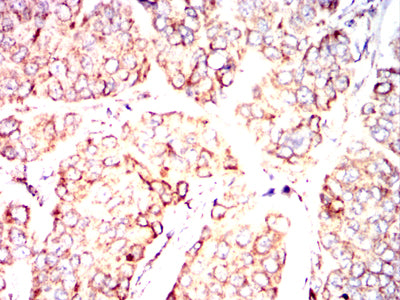

Immunohistochemical analysis of paraffin-embedded human colon cancer tissues using PDHA1 mouse mAb with DAB staining.

Immunohistochemical analysis of paraffin-embedded human breast cancer tissues using PDHA1 mouse mAb with DAB staining.